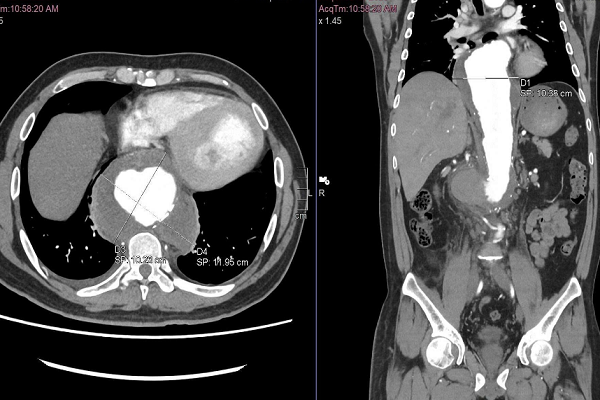

Kết quả chụp CTA cho thấy, bệnh nhân bị vỡ túi phình động mạch chủ ngực – bụng. Khối máu tụ lớn sau phúc mạc với đường kính lên đến 11cm

Kết quả chụp cắt lớp vi tính mạch máu (CTA) nhanh chóng xác định một thực trạng kinh hoàng: anh L. bị vỡ túi phình động mạch chủ ngực – bụng. Khối máu tụ lớn sau phúc mạc với đường kính lên đến 11cm được ví như một "quả bom" khổng lồ đã bắt đầu phát nổ, đe dọa tước đi mạng sống của bệnh nhân trong tích tắc.